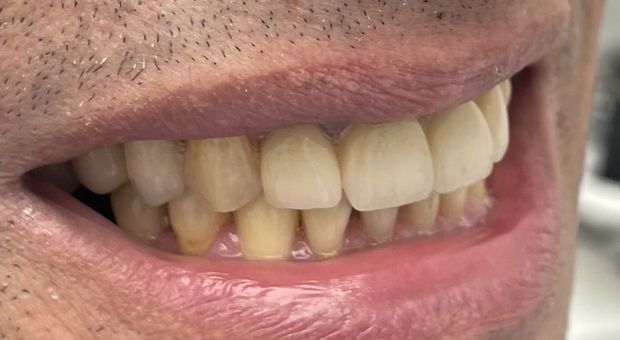

Pełna rekonstrukcja zgryzu, zmiana koloru i kształtu zębów za pomocą koron i mostów cyrkonowych licowanych porcelaną w kolorze BL2.

Metamorfoza uśmiechu w „Hollywood smile”